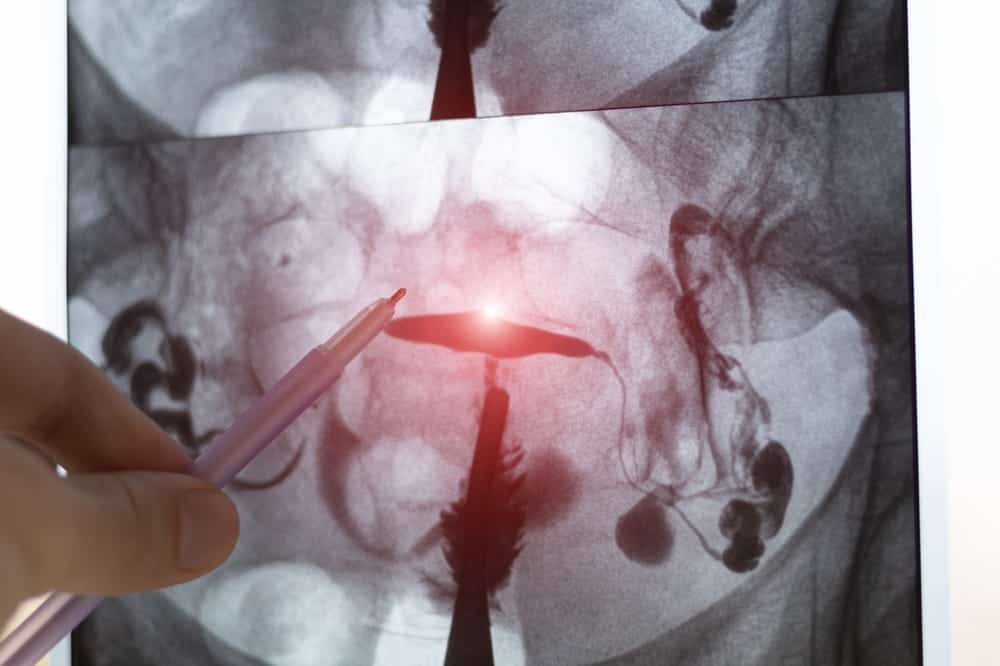

Evaluation of Fallopian Tubes and Uterine Cavity

Especially important for women with prior ectopic pregnancy, these tests help reduce recurrence risk:

- Hysterosalpingography (HSG) to assess whether the remaining fallopian tube is open

- Laparoscopy to directly evaluate adhesions or inflammation

- Hysteroscopy to identify uterine cavity abnormalities affecting implantation